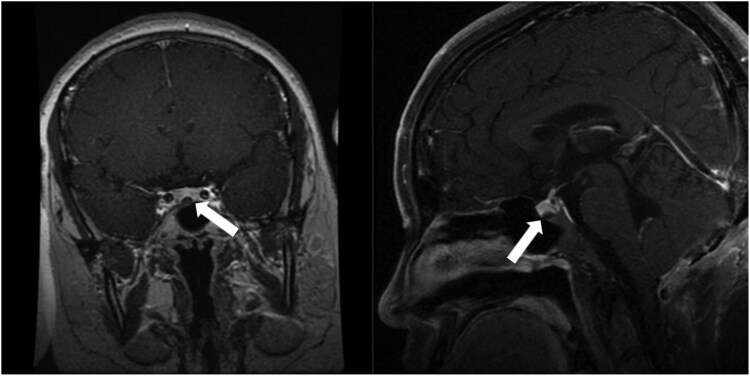

Von Hippel-Lindau (VHL) disease is an autosomal dominant disorder caused by germline pathogenic variants of the VHL gene, which can lead to abnormal growth of blood vessels and cause the development of benign or malignant tumors, as well as cysts in diverse organs. To date, no case reports have documented adrenocorticotropic hormone (ACTH)-secreting adenomas in individuals with VHL disease. We present the case of a 19-year-old female individual with VHL disease who developed an ACTH-secreting adenoma alongside hemangioblastomas in the central nervous system (CNS) and cystic lesions in diverse organ systems. Genetic testing and immunohistochemistry of the pituitary tumor were performed. Genetic testing revealed that the patient carried the familial germline pathogenic variant located in the first exon of the VHL gene (c.227_229del, p.76delF). Immunohistochemical staining of the pituitary tumor demonstrated positive for ACTH, chromogranin A, and synaptophysin, with Ki-67 index at 3%. In addition, tumor cells showed scattered immunoreactivity for the α subunit of hypoxia-inducible factor (HIF-1α). This case suggests that VHL disease might be associated with ACTH-secreting adenomas and broadens the tumor spectrum.

Abstract Image